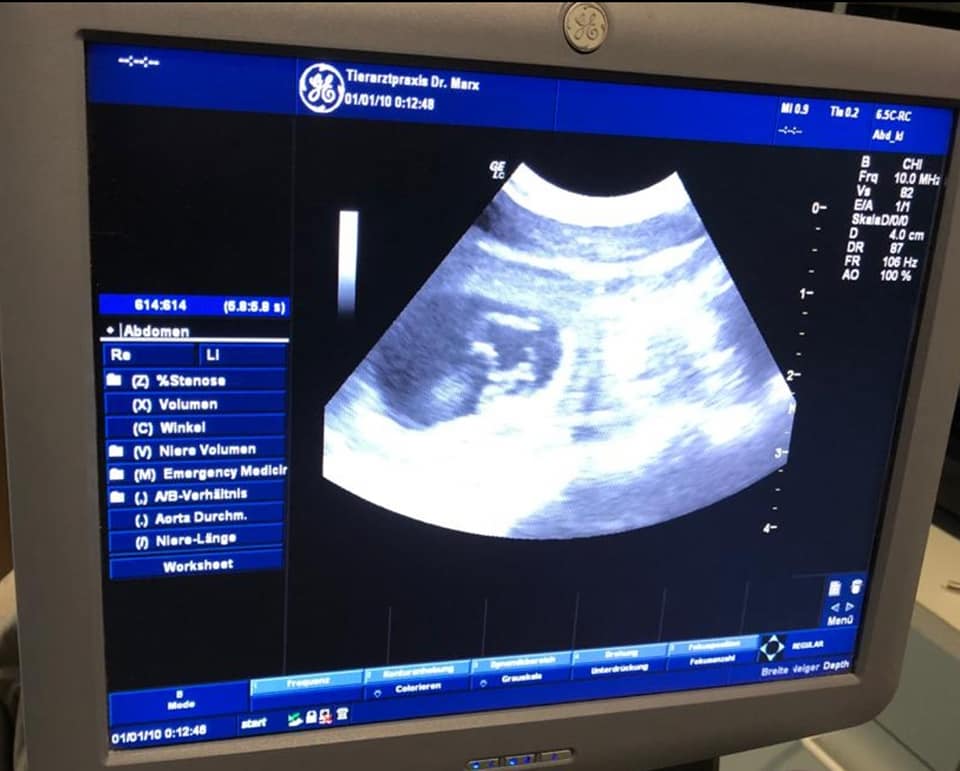

Die Ultraschalluntersuchung am 01.10.2021 ergab das unsere Cleo tragend ist.

Wir erwarten somit Anfang November 2021 unseren C-Wurf.